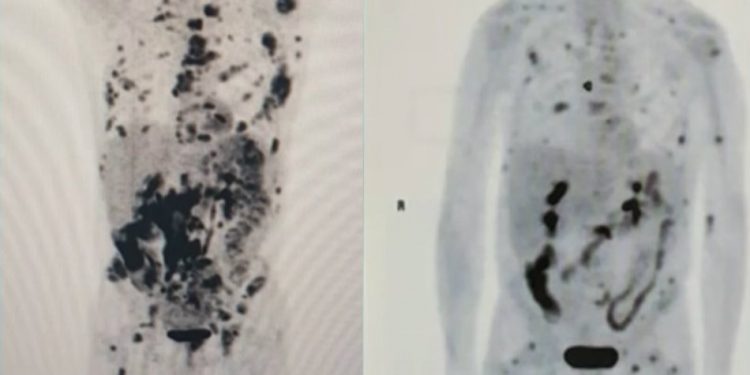

Exames feitos com pouco mais de um mês de diferença mostram o recuo de um linfoma em fase terminal em um paciente de 62 anos. Vamberto Luiz de Castro recebeu um tratamento inédito na América Latina, com uma técnica de terapia genética descoberta no exterior e conhecida como CART-Cell. As informações são do G1.

No início de setembro, segundo a publicação, o corpo do mineiro estava tomado por tumores, mas, nesta semana, a maioria já desapareceu. Segundo os médicos, isso é um indicativo da evolução da terapia. Para pesquisadores do Centro de Terapia Celular (CTC-Fapesp-USP), ligado ao Hospital das Clínicas de Ribeirão Preto, Vamberto está praticamente livre da doença.